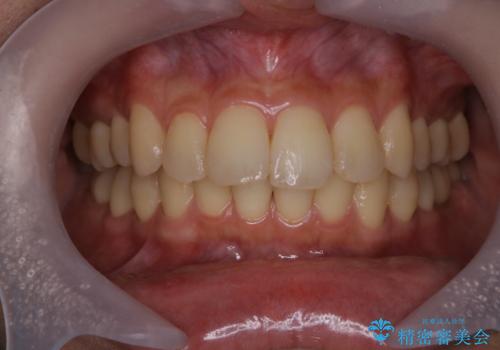

- 見た目をきれいにしたいとのことで来院されました。PMTC60分コースを行いました。

また、PMTCを行うことで、ステインやバイオフィルムが除去され、ご自身本来の歯の色となります。